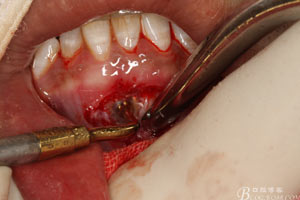

圖11.根尖切除后,并搔刮干凈后的31缺損的骨腔情況

圖12.使用超聲骨刀倒預(yù)備刀頭

圖13.31的根管倒預(yù)備